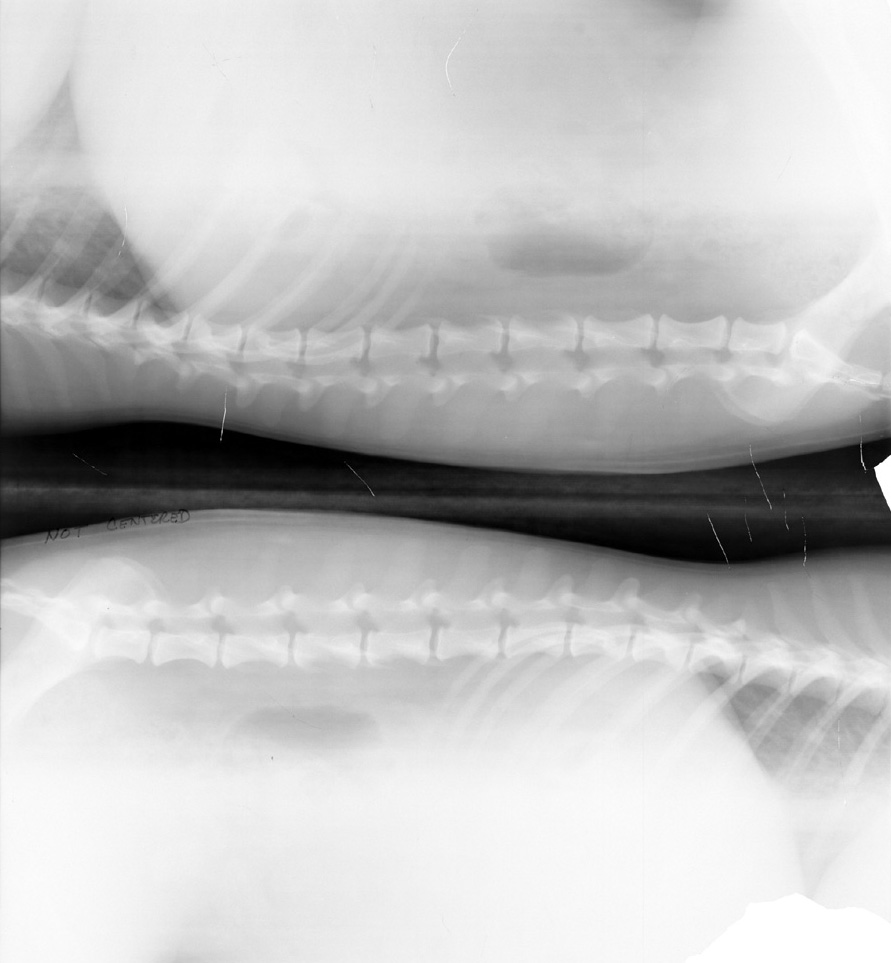

Film folded in cassette during exposure (double image)